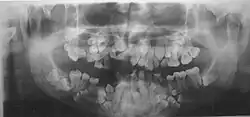

• The permanent teeth include supernumerary teeth. Unless these supernumeraries are removed they will crowd the adult teeth in what already may be an underdeveloped jaw. If so, the supernumeraries will probably need to be removed to make space for the adult teeth. Up to 13 supernumerary teeth have been observed. Teeth may also be displaced. Cementum formation may be deficient.[13]

• Failure of eruption of permanent teeth.

• Crooked teeth